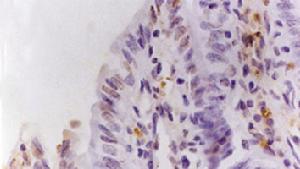

腸中風缺血性結腸炎的病人大都患有心腦血管疾病。犯病時會突然腹痛起來,並有便血。腹痛的性質就好像肚子被什麼人的手緊緊抓任那樣。這種腹痛和便血現象有時可以自行緩解,但又會反覆發作。此症用藥物不能根治,必要時只有考慮將缺血的那段腸子做手術切除。缺血性結腸炎大多發生在高齡老人中,約占91%,而且缺血的腸段大多數位於左半結腸,所以,病人會解出鮮紅色糞便。